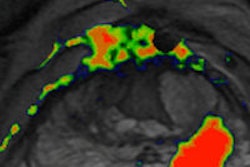

In a study presented at ECR 2014, Dr. Daniele Regge of the Institute for Cancer Research and Treatment in Candiolo shared the institution's experience with a CAD algorithm they developed that yields a color-coded map with per-pixel estimates of cancer probability. Click here to learn how well the system performed.